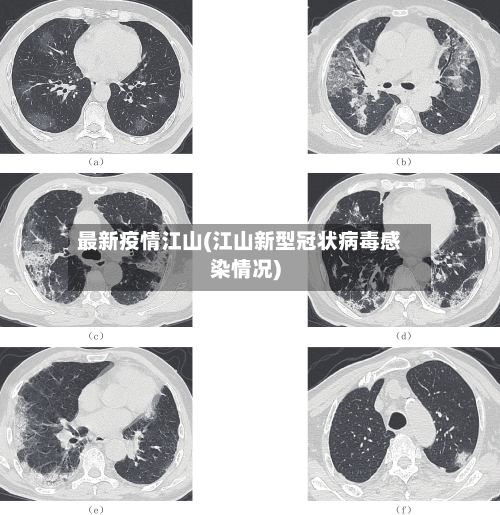

〖壹〗、020年2月19日0-24时 ,衢州市报告无新增新冠肺炎确诊病例。截至2020年2月19日24时,衢州市累计报告新冠肺炎确诊病例21例,累计出院10例 ,现有重症病例2例 。确诊病例中:柯城区2例、衢江区10例 、江山市6例、常山县3例。重症病例:衢江2例。出院病例中:柯城2例、衢江区1例 、江山市4例、常山县3例 。

〖贰〗、020年2月18日0-24时,衢州市报告无新增新冠肺炎确诊病例。截至2020年2月18日24时,衢州市累计报告新冠肺炎确诊病例21例 ,累计出院10例,现有重症病例2例。确诊病例中:柯城区2例 、衢江区10例、江山市6例、常山县3例 。重症病例:衢江2例。出院病例中:柯城2例、衢江区1例 、江山市4例、常山县3例。